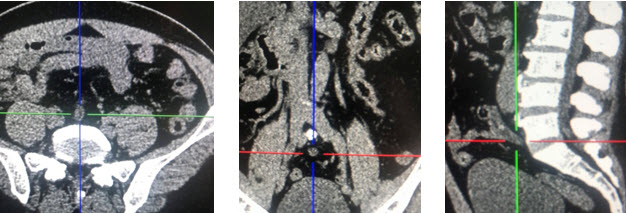

Tại khoa nội tổng hợp bênh nhân tiếp tục được điều trị theo hướng viêm dạ dày cấp với kháng sinh truyền tĩnh mạch, kháng tiết và băng niêm mạc dạ dày tuy nhiên tình trạng bệnh không cải thiện với đau tức liên tục vùng thượng vị , nôn khan, bụng chướng, ghi nhận hố chậu phải mềm. Tiêm Morphin bệnh nhân cũng không dịu đau. 6h ngày 25/4/2020 thăm khám ghi nhận: bệnh nhân không sốt, đau tức thượng vị và quanh rốn, hố chậu phải không đau, nôn khan nhiều, bụng chướng, chưa trung và đại tiện. Bệnh nhân được xử trí đặt thông dạ dày, truyền dịch, chống có thắt, thụt tháo phân. chụp Xquang bụng đứng thấy hình ảnh quai ruột non giữa ổ bụng chướng hơi lớn, không có liềm hơi dưới cơ hoành, không có mức hơi dịch điển hình (Hình 1). Siêu âm bụng lần 2: kết quả: gan nhiễm mỡ, dịch ổ bụng âm tính, làm lại xét nghiệm máu ghi nhận BC 15 G/l, BCĐNTT 83%, Crp 123. Bàn giao tua sau theo dõi tiếp

Xquang bung dung sang

Hình 1. Xquang bụng đứng sáng 25.4.2020